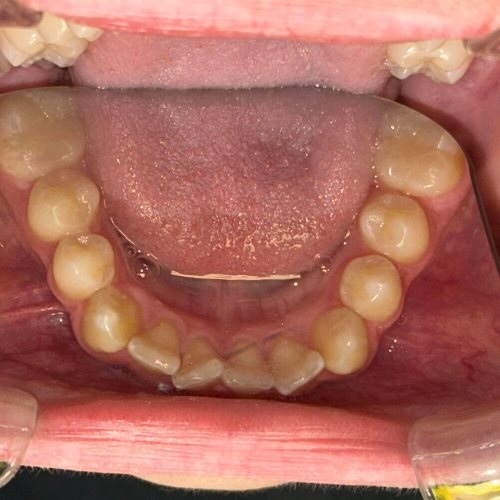

Każdy Pacjent ma inne potrzeby i inną wadę zgryzu, stąd zawsze powinna być przeprowadzana wstępna konsultacja, wyciski/skany, oraz pomiary by jak najlepiej zaplanować cały proces (i czas) leczenia, a przede wszystkim dobrać do potrzeb Pacjenta odpowiedni aparat ortodontyczny.

- wykonania precyzyjnego plan leczenia oraz indywidualnych skanów zębów Pacjenta skanerem wewnątrzustnym,

Aparat Invisalign® w większości przypadków nadaje się dla każdego Pacjenta, który ma zęby wyleczone oraz wyczyszczone z kamienia i osadu.